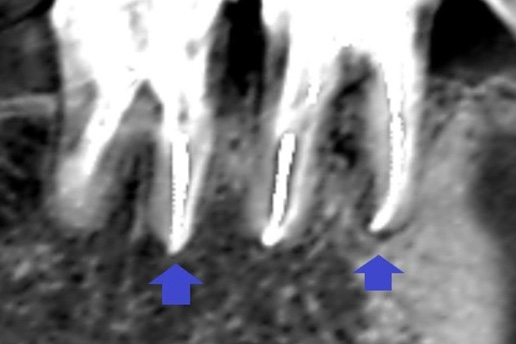

■精密な虫歯治療

詰め物の中が虫歯になっていた。セラミック素材で再治療を行ったケース。